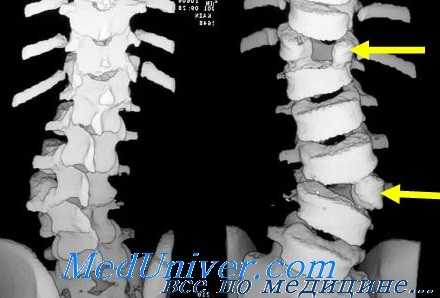

Компьютерная томография (КТ) костей. Диагностические возможности

Простые томограммы ценны при диагностике травм конечностей в областях, в которых рентгенологическое изображение конечности в трех плоскостях сложно для интерпретации.

Метод приемлем для любого участка тела, где обычные рентгенограммы малоинформативны. В практике экстренной медицины томограммы часто необходимы в диагностике травм позвоночника. Тем не менее метод пригоден и при некоторых видах травм конечностей. К ним относят переломы проксимального суставного конца большеберцовой кости, когда по обзорным рентгенограммам трудно определить степень смещения.

При компьютерной томографии (КТ) многочисленные отдельные рентгенологические изображения с помощью компьютера собраны в двухмерное изображение костей и мягких тканей. Большое преимущество метода над обычной рентгенографией заключается в том, что улучшается изображение мягких тканей и появляется возможность получать изображения в аксиальной проекции.

Этот метод революционизировал рентгенографию черепа и позвоночника и оказался эффективен и в диагностике травматических и нетравматических поражений скелета и других отделов.

КТ эффективна в оценке переломов костей таза. Аксиальная проекция дает лучший обзор при передних и задних смещениях. Метод хорошо выявляет вертлужную впадину; данные КТ могут оказать решающее влияние на выбор открытой репозиции и последующих лечебных мероприятий. Однако следует иметь в виду стоимость этой процедуры и дозу облучения, получаемую больным, поэтому нецелесообразно применять ее при всех переломах таза.

КТ можно применить при подозрении на перелом головки и шейки бедренной кости без смещения. Аксиальная проекция дает хороший обзор головки бедренной кости и позволяет определить взаиморасположение ее и вертлужной впадины. Компьютерная томография дает возможность увидеть невидимые на простых рентгенограммах костные фрагменты и изменения суставных поверхностей.

Есть данные, что в оценке переломов проксимального эпифиза большеберцовой кости КТ может превосходить обычную томографию. Rafii и соавт. сообщили, что КТ дает более точную информацию о степени смещения отломков и для значительного процента больных с этим повреждением, обследованных обоими методами, решающим образом меняла план лечения.